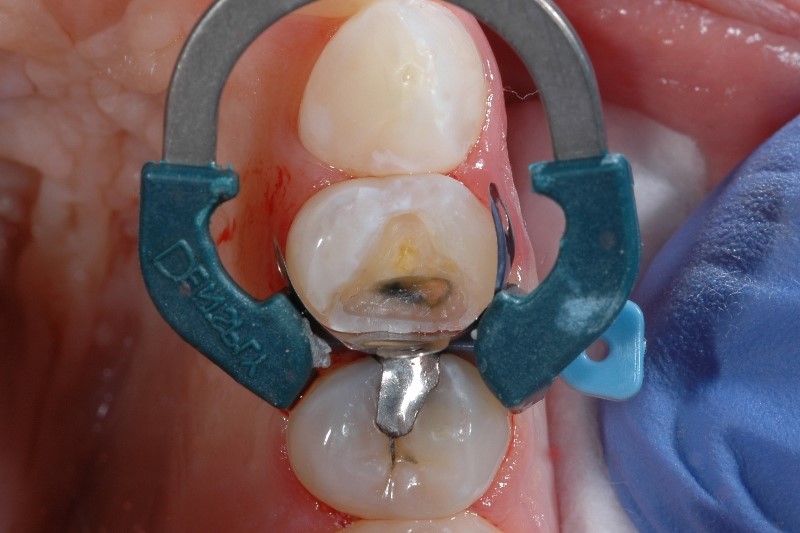

What causes post-op sensitivity after composite fillings? Quite a few things, actually - placing composite resins is a complex procedure considering the nature of dentin is close to the pulp, and some studies have estimated sensitivity occurs after 10-15% of posterior composite restorations.1

Studies4 have shown that polymerization shrinkage of the resin is one of the top causes of sensitivity post-op, but that’s not the only scenario where incomplete material coverage can lead to post operative sensitivity. It’s important to cover the internal surface completely and uniformly with an adhesive. You’ll know you’ve done this correctly if the surface appears glossy rather than matte.